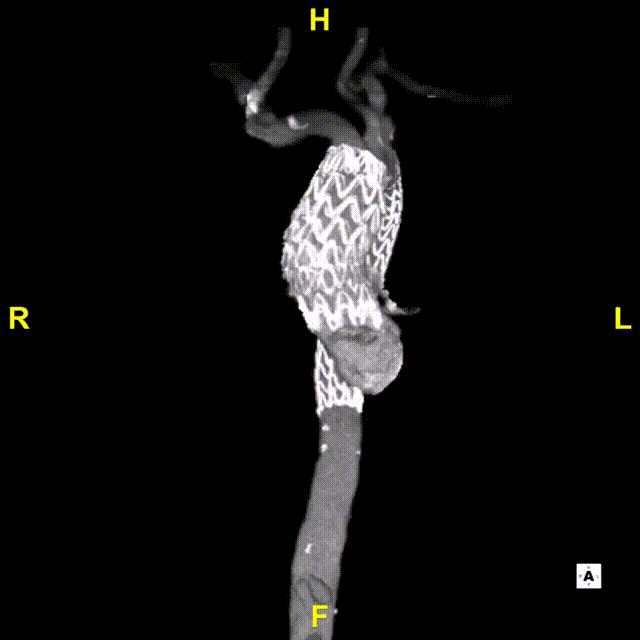

术后随访

患者出院前进行CTA复查,可见溃疡隔绝完全,弓上分支血管及冠状动脉通畅。

术后3D动态

术后3D动态 grey